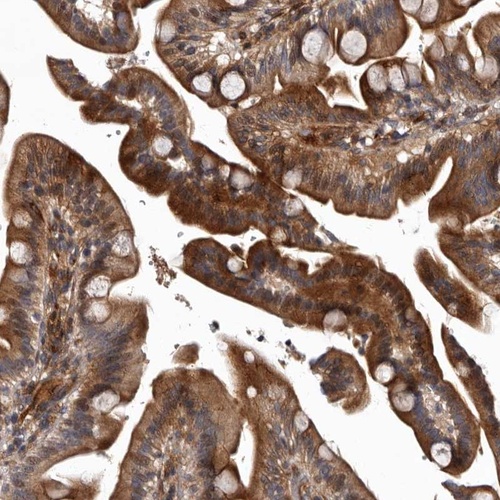

Immunohistochemical staining of human duodenum shows distinct cytoplasmic positivity in glandular cells.